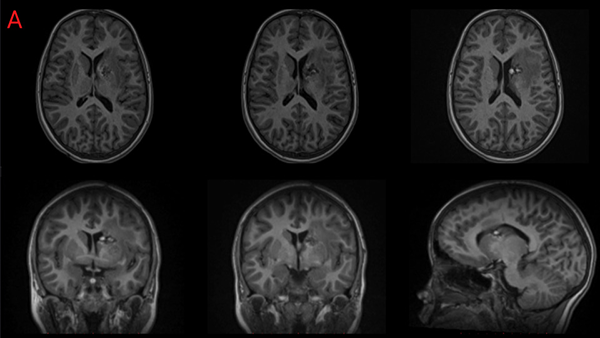

La paciente de 12 años presentó cefaleas, hemiparesia y pérdida de conciencia aguda que requirió soporte de Asistencia Respiratoria Mecánica durante tres días, dos meses previos a la cirugía. Debido al volcado ventricular se colocó un Drenaje Ventricular al exterior. Luego del episodio agudo la paciente se recuperó sin déficit motor. Mediante Resonancia Magnética por Imágenes (RMI) se diagnosticó un Cavernoma adyacente a la CI y sobre el Núcleo Caudado (NC) (Figura 1 A, B y C). El estudio de la RMI por Tensor de Difusión (Tractografía) expuso que la vía motora izquierda no estaba interrumpida completamente, quizá desplazada hacia lateral respecto de la rodilla de la CI (Figura 2).

Para el presente caso se incorporaron las imágenes de RMI al equipo de neuronavegación electromagnético provisto de una cánula de aspiración maleable de 3 mm con cursor de navegación “on tip” incorporado (Faigon © origen Alemania). Se trazó la trayectoria marcando como blanco el sitio de aparente irrupción de la sangre en la pared lateral de la prolongación frontal durante el episodio hemorrágico de presentación del Cavernoma (Figura 3).